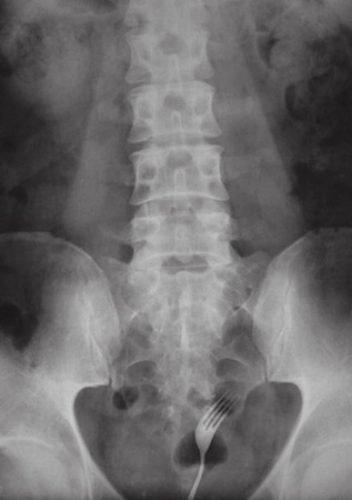

4-Um garfo

O objeto também já foi encontrado outras vezes dentro de pessoas mas havia sido ingerido e não inserido, se é que me entendem. O garfo, consideravelmente pontudo e cortante, foi colocado dentro do ânus de um homem por sua esposa como uma forma de “apimentar” a relação.